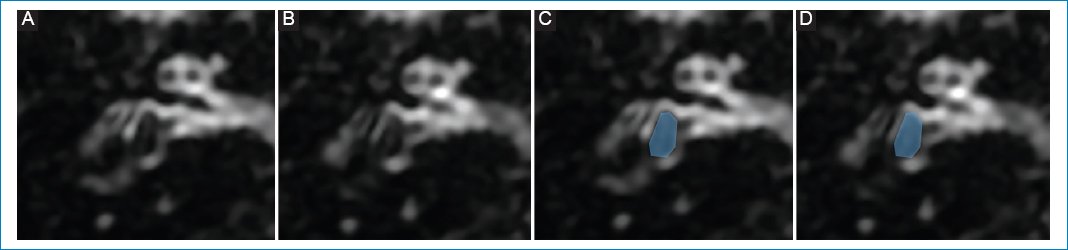

Figura 2. (A y B) Cóclea y vestíbulo normal; representación esquemática en C y D. A nivel coclear (puntos naranjas), la escala media o conducto coclear suele ser mínimamente visible; a nivel vestibular, el sáculo y el utrículo ocupan menos del 50% del área total del vestíbulo membranoso, siendo el sáculo (círculo amarillo) de menor tamaño que el utrículo (círculo verde).

De forma retrospectiva revisamos 362 estudios de RM con protocolo de hidrops, con un total de 724 laberintos. Se utilizó un equipo 3T (Discovery 750, GE, Wisconsin, USA) con bobina de cerebro de 32 canales de recepción para maximizar la relación señal/ruido. Primero se realizó un examen dedicado al oído sin contraste y tras la administración de Gd se obtuvo una secuencia volumétrica T1 del oído interno y de todo el cerebro. Luego de 4 h de la inyección (sin exceder 3,5-4,5 h) se adquirió la secuencia de hidrops. Para la obtención de imágenes de hidrops se utilizó la secuencia 3D-FLAIR, que es una técnica de inversión-recuperación que tras la inyección de contraste intravenoso (Gd) permite la anulación selectiva del espacio endolinfático. De esta manera se genera una imagen en la que se puede diferenciar la endolinfa, de señal hipointensa, de la perilinfa, de señal hiperintensa (realzada con Gd), mientras que el hueso circundante muestra una intensidad de señal similar a la endolinfa (Fig. 2). Las variaciones en el tiempo de inversión influyen en el tamaño aparente de las estructuras endolinfáticas, y por ello es recomendable que sea entre 2000 y 2500 ms45. Debido al pequeño calibre de las estructuras endolinfáticas, aplicamos un grosor de corte de 0,8 mm. Las secuencias de hidropesía se obtuvieron en el plano axial paralelo al canal semicircular lateral y se interpretaron junto con una secuencia 3D fuertemente ponderada en T2 del oído interno como referencia del espacio total de líquido del laberinto. Los tiempos de exploración para la secuencia 3D-FLAIR fueron de aproximadamente 8-9 min aplicando ángulos de inversión variables. Los parámetros de la secuencia 3D-FLAIR pueden variar y se resumen en la table 1.